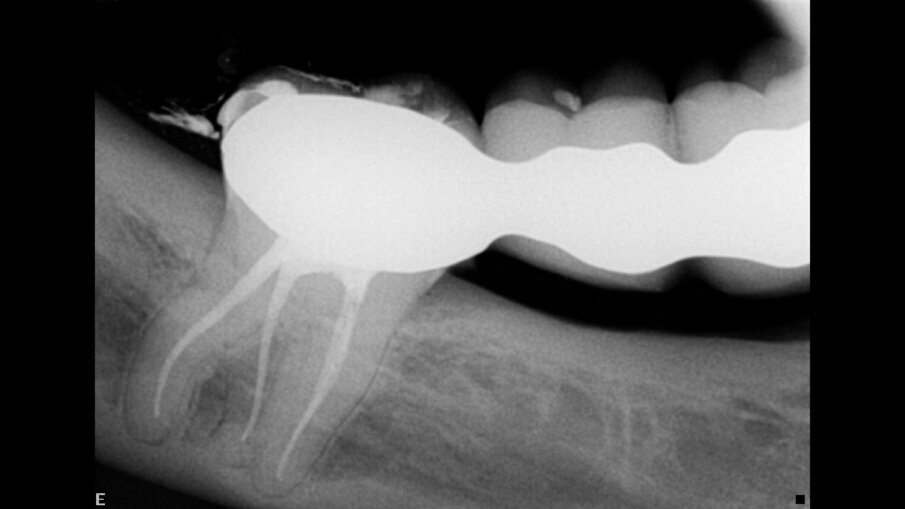

Isti pacijent je imao fistulu u bukalnoj zoni na nivou bifurkacije mandibularnog molara, nastalu zbog toga što su okluzalni kontakti bili previsoki i nisu bili podešeni nakon postavljanja inleja na maksilarni molar (Sl. 8a-b). Ovo je izazvalo aktivaciju supstance P koja je potom stvorila kalcifikacije u maksilarnom molaru i nepovratnu upalu mandibularnog molara - efekte mikrotraume.

Koristeći endodontski režim u DTX Studio Clinic (Sl. 9), pregledan je svaki snimak i rez, tražeći razlog za fistulu mandibularnog molara. Mogući uzrok fistule može biti kompleks bočnih kanala koji se vidi u koronarnom delu distalnog korena (Sl. 10). Terapija kanala korena je započeta korišćenjem Traverse i ZenFlex turpija u istom redosledu koji je korišćen za slučaj 1, a izvršena je 3D obturacija sa Elements IC (Sl. 11).

Sl. 8a: Radiografija pre operacije koja prikazuje kalcifikovanu pulpnu komoru i radiolucenciju u oblasti bifurkacije; Sl. 8b: Radiografija pre operacije koja pokazuje fistulu okrenutu ka koronarnom delu kanala korena

Sl. 9: Endodontski režim u DTX Studio Clinic u različitim delovima za analizu slučaja

Sl. 10: Horizontalni prikaz debljine samo 0,5 mm koji prikazuje složen sistem bočnih kanala u koronarnom delu distalnog kanala

Sl. 11a: Rekonstrukcija kosti sa DTX Studio Clinic koja pokazuje defekt kosti u koronarnoj oblasti; Sl. 11b: Rendgen snimak neposredno posle operacije koji pokazuje bočne kanale ispunjene u koronarnom delu distalnog kanala